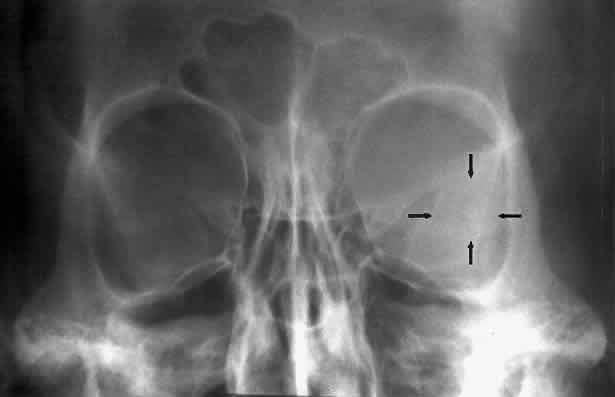

The superior orbital fissure has interpersonal and intrapersonal variations. The fissure should be symmetric, but there is no good measurement that identifies pathology, other than marked asymmetry. The fissure can be enlarged by infraclinoid aneurysm, carotid-cavernous fistulas, pituitary tumors, and meningiomas.26 Less common causes for enlargement include hemangiomas, lymphoma, mucocele of the sphenoid sinus, and neurofibromatosis (Fig. 15).

Fig. 15. Enlargement of the left superior orbital fissure (arrow) by neurofibromatosis. The Caldwell projection gives the best view of this fissure.

The optic foramen should measure 6 mm vertically and 5 mm horizontally. Asymmetry greater than 1 mm or a vertical dimension greater than 6.5 mm is considered abnormal.15,27 Ninety-eight percent of patients have optic canals that vary by less than 1 mm.27 Concentric enlargement of the foramen and optic canal can be seen with optic nerve gliomas, meningiomas, neurofibromatosis, and less commonly an aneurysm of the ophthalmic artery (Fig. 16). A decrease in the optic foramen and canal dimension can be seen in fibrous dysplasia, Paget's disease, hyperostosis secondary to a meningioma, or microphthalmos (Fig. 17, Table 1).

Fig. 16. Oblique apical projections showing the optic foramen. The left optic foramen has concentric enlargement from an optic nerve glioma. The foramen should not have greater than 1 mm of asymmetry.